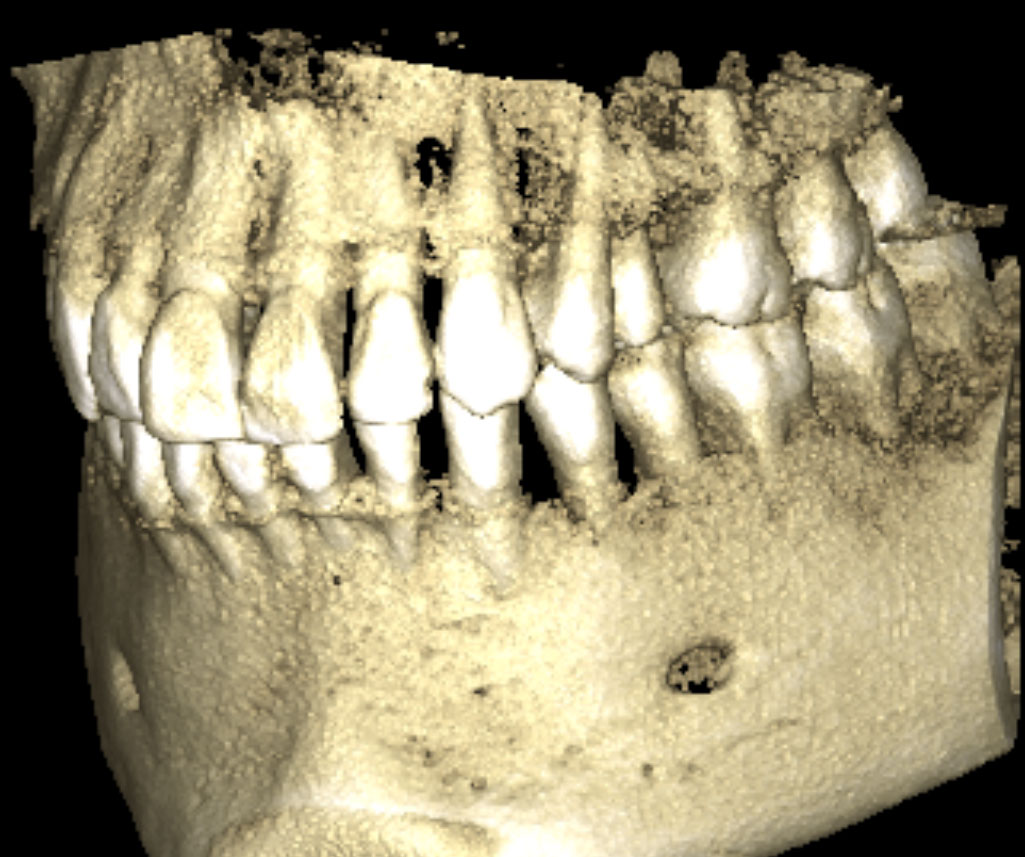

Panoramaröntgen und DVT

strahlenreduziertes 3D Zahnröntgen am Zahnambulatorium Wienerberg City in Wien

Mit unseren hauseigenen digitalen Volumentomographen werden Panoramaröntgen, 3D-(DVT)-Bilder und Kleinbilder bei niedriger Strahlenbelastung in höchster Auflösung und Qualität dargestellt.